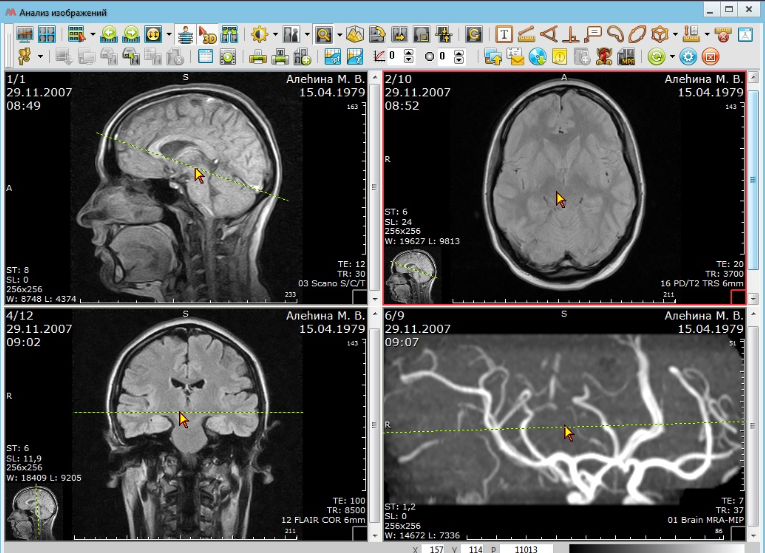

АПК АрхиМед отличается надежностью и широким функционалом. Простой и удобный интерфейс поможет эффективно организовать работу с исследованиями. С нашей системой получить качественное исследование стало проще и быстрее.

Некоторые функциональные возможности и характеристики программного обеспечения АПК АрхиМед

- Раскладка серий изображений

- Функция 3D курсора (автоматическое указание местоположения выбранной точки изображения на изображениях других серий с синхронизацией при навигации)

- Мультипланарная реконструкция (MPR) выбранной серии изображений во взаимно перпендикулярных плоскостях